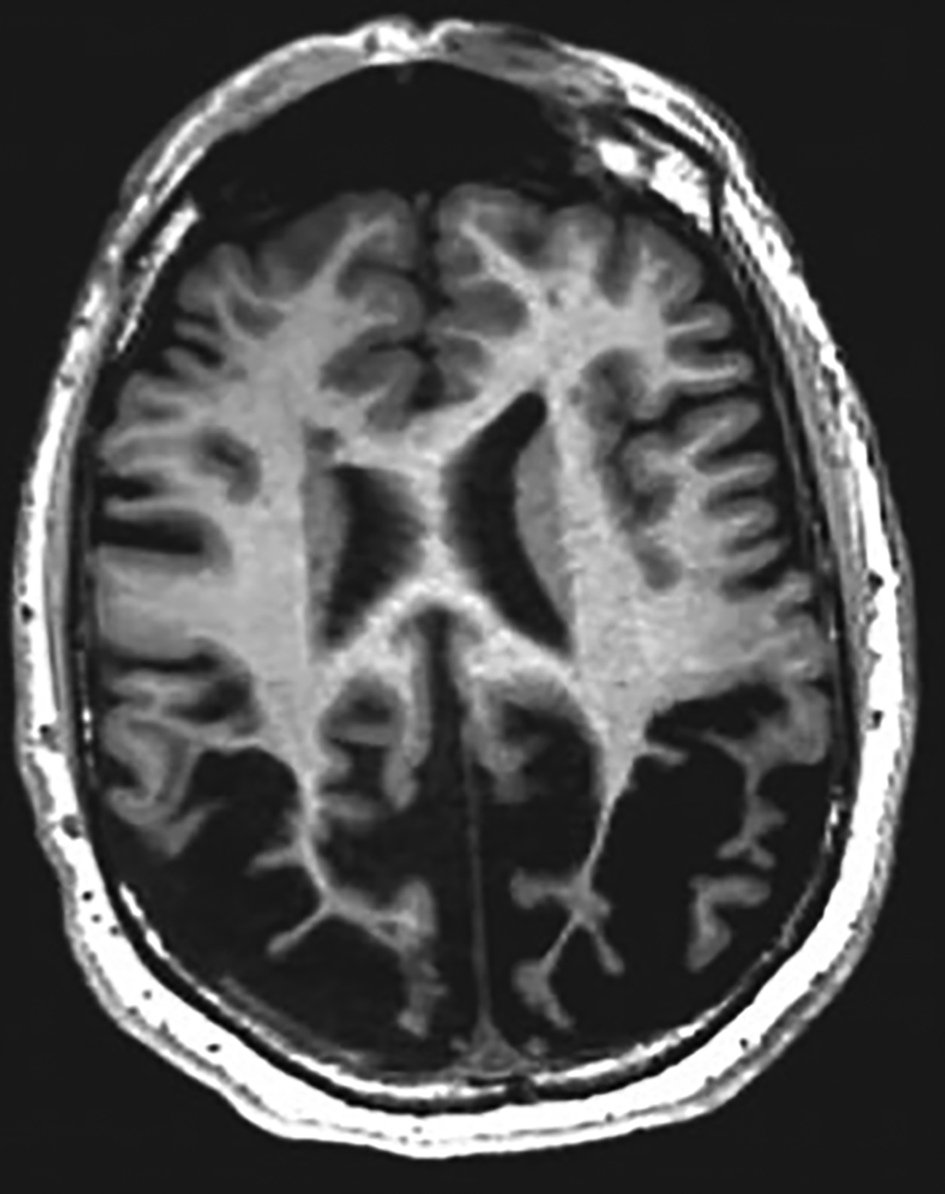

From the pattern of cognitive difficulties in our case we were considering a lesion involving the posterior aspects of the cerebral hemispheres. On the MRI brain scan there was severe atrophy of the parietal lobes, which was marked when compared with the surrounding parenchymal volume. This fits with our pattern of neurocognitive defects (Fig. 1 shows an illustrative MRI).

FIG 1 A magnetic resonance imaging scan of the brain showing posterior cortical atrophy resulting in visual impairment. © 2019 Elsevier. Reprinted with permission from Keuss et al (2019).

The most likely cause of this pattern of atrophy and the clinical presentation in our patient would be posterior cortical atrophy. This condition, also known as Benson syndrome, is often related to an Alzheimer disease phenotypic variant, although Lewy body dementia or even prion disease can also cause it (Crutch Reference Crutch, Lehmann and Schott2012; Holden Reference Holden, Bettcher and Pelak2020). The posterior lobar predilection leads to the classic symptoms of parieto-occipital dysfunction.